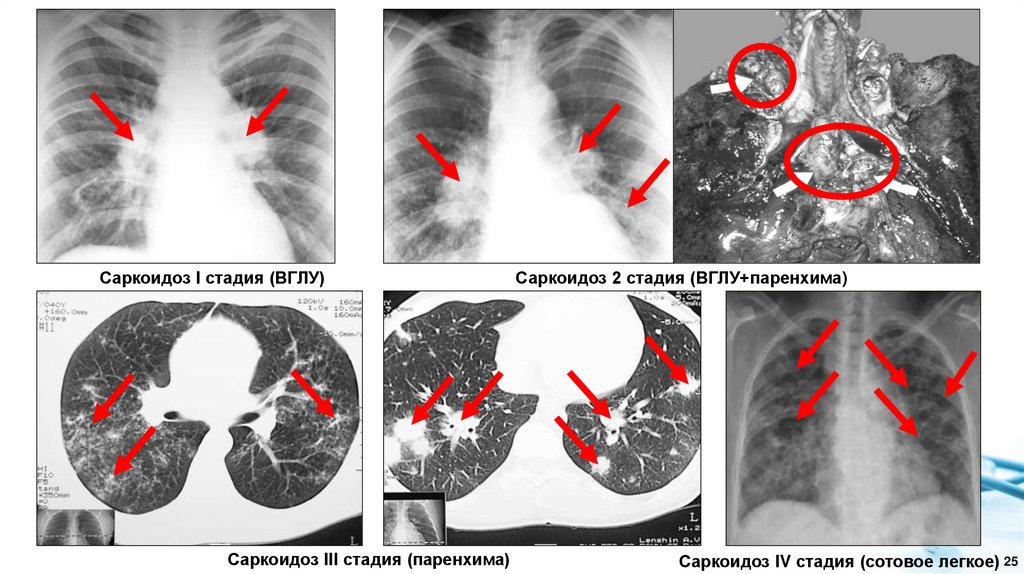

2. Классификация внутригрудного саркоидоза, основанная на

данных лучевого обследования

= медиастинальная

форма

= медиастинальнолегочная или

бронхопульмональная

Компьютерная томография (КТ) органов грудной клетки более точно характеризует

распространенность и характер патологических изменений, чем рентгенографическое

исследование. Выявленные при КТ признаки внутригрудного саркоидоза дополняют

рентгенологическую стадию болезни. При построении диагноза перечисляются все органы и

системы, в которых были обнаружены признаки саркоидоза. Рентгенологическая классификация

не может рассматриваться как стадийность клинического течения саркоидоза.

Саркоидоз I стадия (ВГЛУ)

Саркоидоз III стадия (паренхима)

Саркоидоз 2 стадия (ВГЛУ+паренхима)

Саркоидоз IV стадия (сотовое легкое) 25